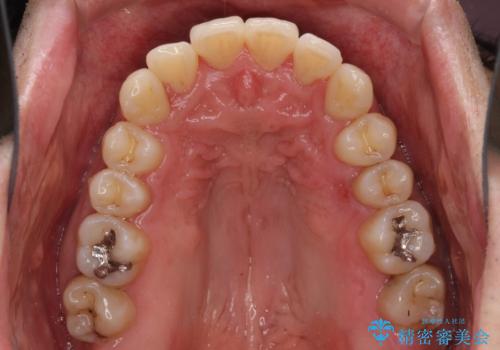

- 上下前歯のデコボコを気にして来院された患者様です。

下顎骨が顕著な左右差を持って成長したため、右側にずれている状態でした。

デコボコは抜歯をすることなく解消できる程度であったため、インビザラインにより矯正治療を行うこととしました。